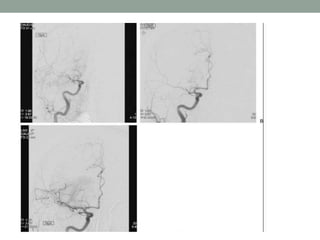

Preventive Endovascular Stroke Treatment

Asymptomatic Carotid Stenosis

• 1. Patients with asymptomatic carotid stenosis should be

prescribed daily aspirin and a statin. Patients should also be

screened for other treatable risk factors for stroke, and

appropriate medical therapies and lifestyle changes should be

instituted (Class I; Level of Evidence C).

• 2. In patients who are to undergo CEA, aspirin is recommended

perioperatively and postoperatively unless contraindicated

(Class I; Level of Evidence C).

• 3. It is reasonable to consider performing CEA in asymptomatic

patients who have >70% stenosis of internal carotid artery if

risk of perioperative stroke, MI, and death is low (<3%).

However, its effectiveness compared with contemporary best

medical management alone is not well established (Class IIa;

Level of Evidence A).

• 4. It is reasonable to repeat duplex ultrasonography annually by

a qualified technologist in a certified laboratory to assess the

progression or regression of disease and response to therapeutic

interventions in patients with atherosclerotic stenosis >50%

(Class IIa; Level of Evidence C)

• 5. Prophylactic CAS might be considered in highly selected

patients with asymptomatic carotid stenosis (minimum, 60% by

angiography, 70% by validated Doppler ultrasound), but its

effectiveness compared with medical therapy alone in this

situation is not well established (Class IIb; Level of Evidence

B)

• 6. In asymptomatic patients at high risk of complications for

carotid revascularization by either CEA or CAS, the

effectiveness of revascularization versus medical therapy alone

is not well established (Class IIb; Level of Evidence B).

• 7. Screening low-risk populations for asymptomatic carotid

artery stenosis is not recommended (Class III; Level of

Evidence C).

Symptomatic Carotid Stenosis:

Recommendations

• 1. For patients with a TIA or ischemic stroke within the past 6

months and ipsilateral severe (70%–99%) carotid artery stenosis

as documented by noninvasive imaging, CEA is recommended

if the perioperative morbidity and mortality risk is estimated to

be <6% (Class I; Level of Evidence A).

• 2. For patients with recent TIA or ischemic stroke and ipsilateral

moderate (50%–69%) carotid stenosis as documented by

catheter-based imaging or noninvasive imaging with

corroboration (eg, magnetic resonance angiogram or computed

tomography angiogram), CEA is recommended depending on

patient-specific factors, such as age, sex, and comorbidities, if

the perioperative morbidity and mortality risk is estimated to be

<6%(Class I; Level of Evidence B)

• 3. When the degree of stenosis is < 50%, CEA and CAS are not

recommended (Class III; Level of Evidence A).